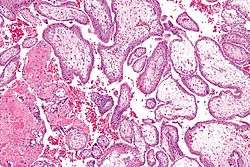

![]() Micrograph showing chorionic villi. Intermediate magnification. H&E stain. | |

Chorionic villi are villi that sprout from the chorion to provide maximum contact area with maternal blood.

They are an essential element in pregnancy from a histomorphologic perspective, and are, by definition, a product of conception. Branches of the umbilical arteries carry embryonic blood to the villi. After circulating through the capillaries of the villi, blood returns to the embryo through the umbilical vein. Thus, villi are part of the border between maternal and fetal blood during pregnancy.

The bulk of the villi consist of connective tissues that contain blood vessels. Most of the cells in the connective tissue core of the villi are fibroblasts. Macrophages known as Hofbauer cells are also present.